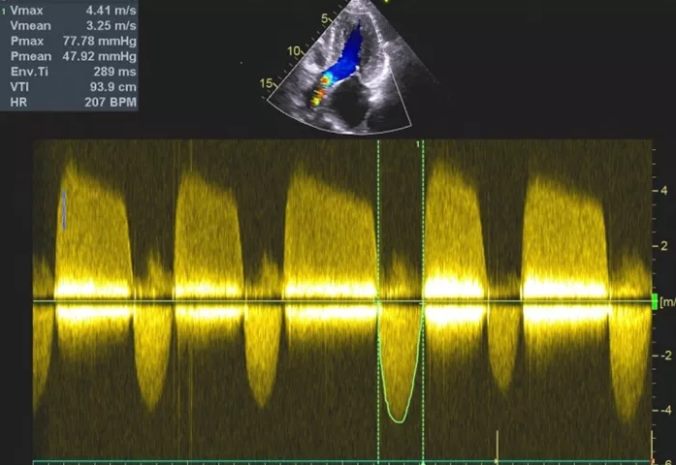

术后心脏超声

患者恢复两天后,专家们准备为她解决另一个问题——主动脉瓣重度狭窄、重度关闭不全。因为准备充分,随后的TAVR手术依然顺利且完美!TAVR手术未对冠脉造成任何影响,且完美解决的主动脉瓣的狭窄及关闭不全。患者术后当天下午即可拔除气管插管并完全清醒,很快康复出院。